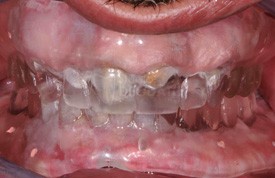

Provvisorio sup .ed inf. fisso in resina

Provvisorio fisso in resina consegnato al paz.